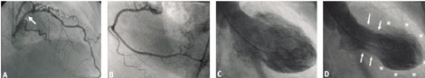

Behandling inleddes med diuretika, ACE-hämmare och ökad dos betablockerare. Koronarangiografi ett dygn efter inläggning visade ateromatösa förändringar i vänster koronarartär med en gränssignifikant stenos i vänster huvudstam (LMS), uppmätt till 47 procent, samt måttliga förändringar i den proximala delen av främre nedåtstigande koronarartären (LAD). Höger kranskärl var normalt (Figur 3 A och B). Vänsterkammarangiografi visade markerad hypokinesi i de anteriora, anterolaterala, apikala och inferiora delarna av vänster kammare samt hyperkinesi i de basala delarna, resulterande i en påtaglig ballonering av den apikala hälften av vänster kammare under systole (Figur 3 C och D).

Ytterligare utvärdering av LMS och proximala LAD med intrakoronar tryckmätning och bestämning av »fractional flow reserve« (FFR) under adenosinprovokation samt intravaskulärt ultraljud utfördes. FFR distalt om LMS och LAD var 0,89, vilket hemodynamiskt motsvarar en icke-signifikant stenosering. Undersökning med intravaskulärt ultraljd visade påtagliga ateromatösa förändringar i LMS med en sannolikt signifikant stenos, där minsta diametern var 2,6 mm, minsta arean 4,7 mm2 och areastenosen 75 procent. Det förelåg inga tecken till akut koronar patologi såsom plackruptur, fyllnadsdefekter eller trombos i LMS eller i proximala LAD (Figur 4 A och B). Ekokardiografisk undersökning verifierade ballonering av den apikala hälften av vänsterkammaren.